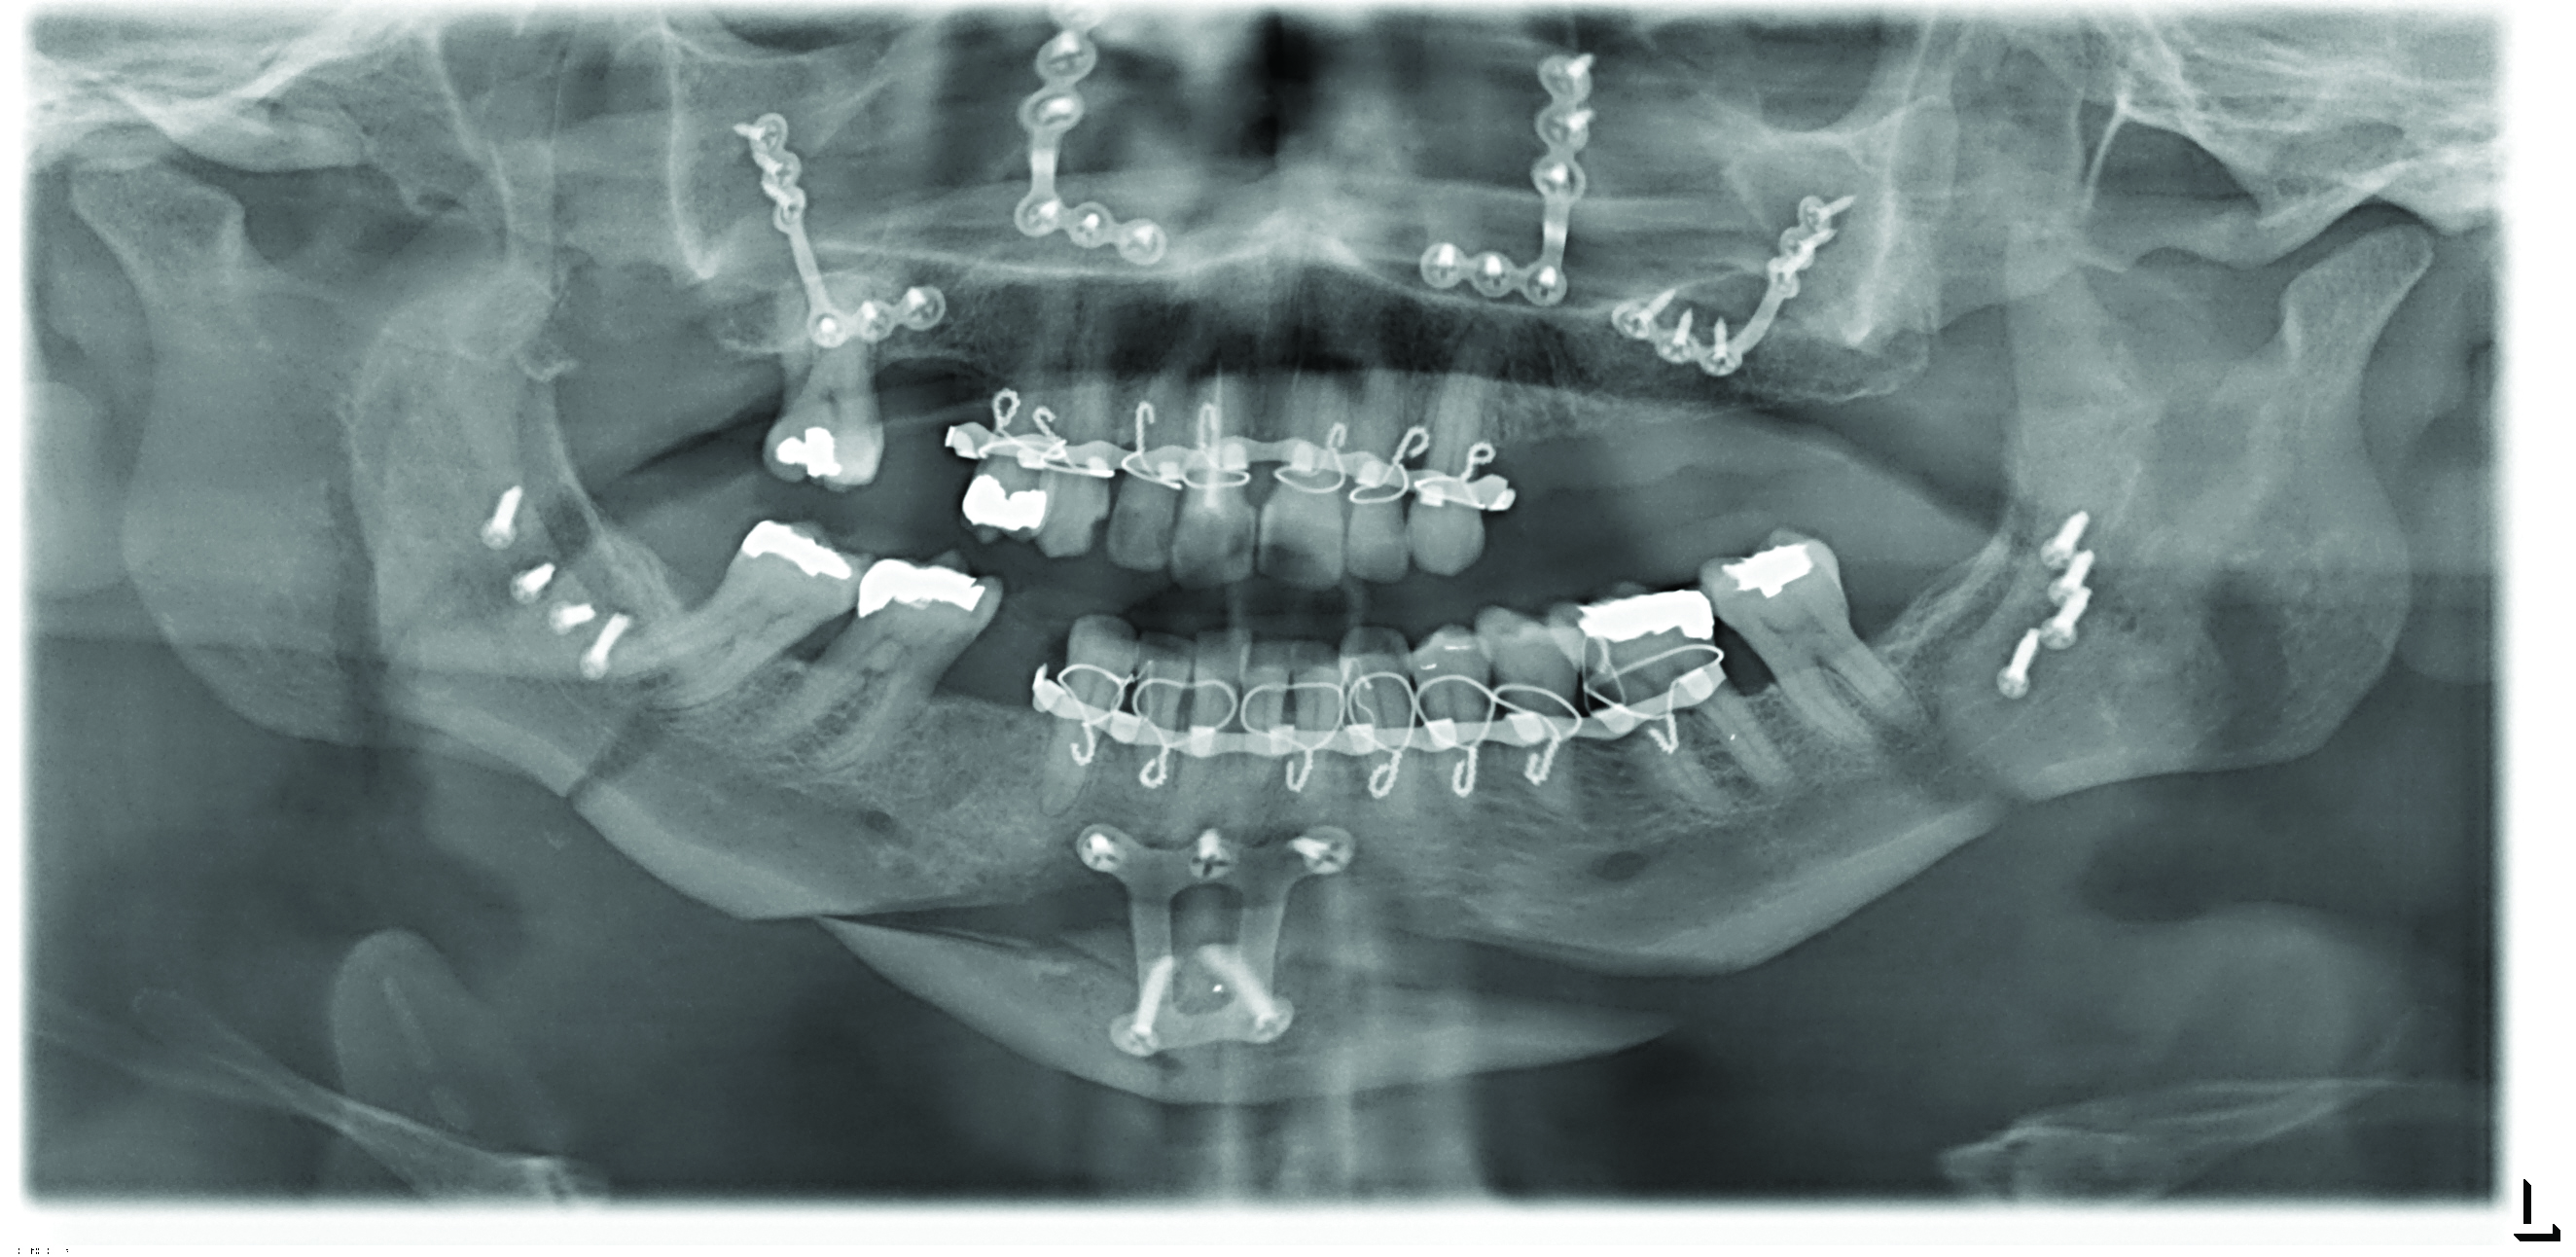

In contrast to soft-tissue surgery, greater success has been reported for surgery that increases upper airway size by repositioning anteriorally the maxilla and/or mandible (Figure 12 and 13). Maxillomandibular advancement surgery for OSA involves one or more of the following: Le Fort I osteotomy, in which the maxilla is moved forward; bilateral split sagittal osteotomy, in which the body of the mandible is moved forward; and anterior inferior mental osteotomy, in which the chin is moved forward (Figure 14).65,66,67 Orthodontics is required before and after the surgery. The surgery is usually reserved for patients with severe OSA who cannot tolerate CPAP, and has been reported successful in 65-100% of patients depending on the definition of success. Unlike CPAP and oral appliances, the surgery attempts to cure, rather than manage, OSA, and compliance to therapy is 100%.

Fig 14. Postsurgical panographic radiograph showing surgical osteotomies and hardware stabilizing the maxilla, mandible, and chin in their new positions.

Figure 14